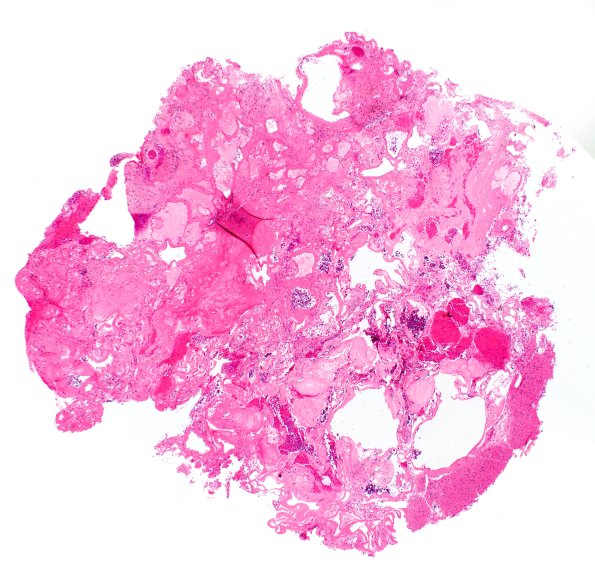

Washington University Experience | VASCULAR | Cavernous Angioma | 30B Cavernous angioma (Case 30) H&E 2X

An H&E-stained section of the left frontal lesion shows multiple dilated thin walled channels. Brain parenchyma around and in the lesion shows glial cells with little hemosiderin deposition. (H&E)